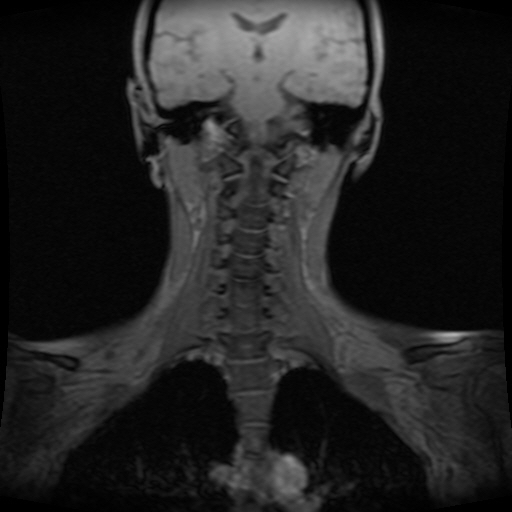

• 1번 째 사진

• 2번 째 사진

• 3번 째 사진

• 4번 째 사진

• 5번 째 사진